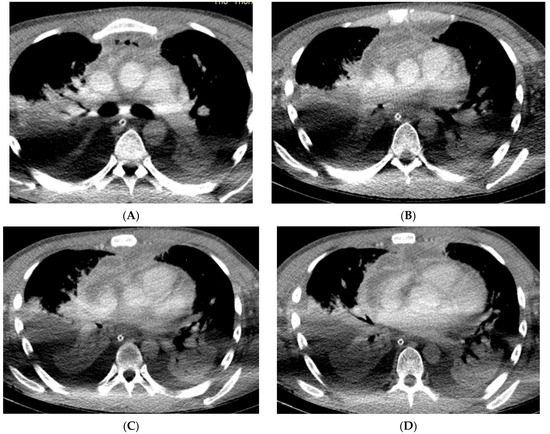

| Neck CT | Pus collection - in the left submandibular area - around the hyoid bone - around the left piriform recessus - around the thyroid cartilage - around the sternocleidomastoid muscle | Presence of a gas collection with delamination of the soft tissues of the neck in the area of the parapharyngeal space on the left Gas collections in - both palatine tonsils - anterior cervical space - left carotid space up to the level of the aortic arch - bilateral submandibular and sublingual space | Multiple air collections that stratify the tissues of the neck on the right side | Multiple air collections that stratify the superficial and deep tissues of the neck and enter the mediastinum |

| Chest CT | pus collection: ventral from the thyroid gland measuring 68/14 mm, with a density of 34–40 HU reaching the carina | Purulent collection starting from the neck and reaching the anterior mediastinum above the carina, presence of gas collections | Multiple air collections involving all departments of the anterior mediastinum above the carina | Massive pneumomediastinum, presence of fluid-purulent collections in the anterior and posterior lower mediastinum below the carina |